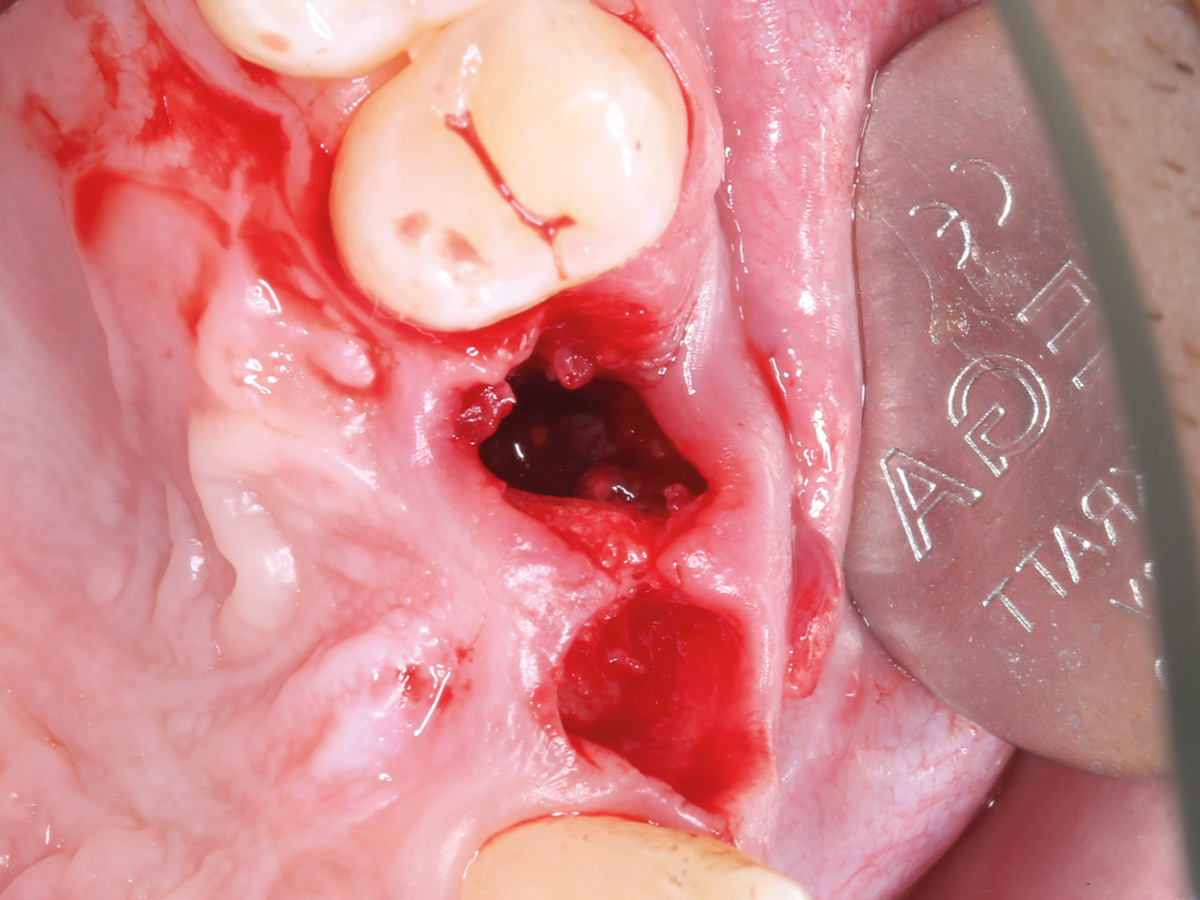

Abbildung 1

Klinische Ausgangssituation lateral, spontane Blutung.

Abbildung 3

Leere Alveole nach atraumatischer Extraktion.